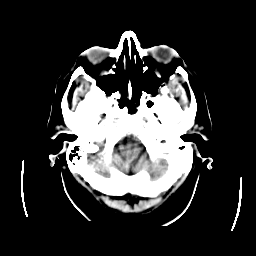

CT Study #2 -- Slice #4